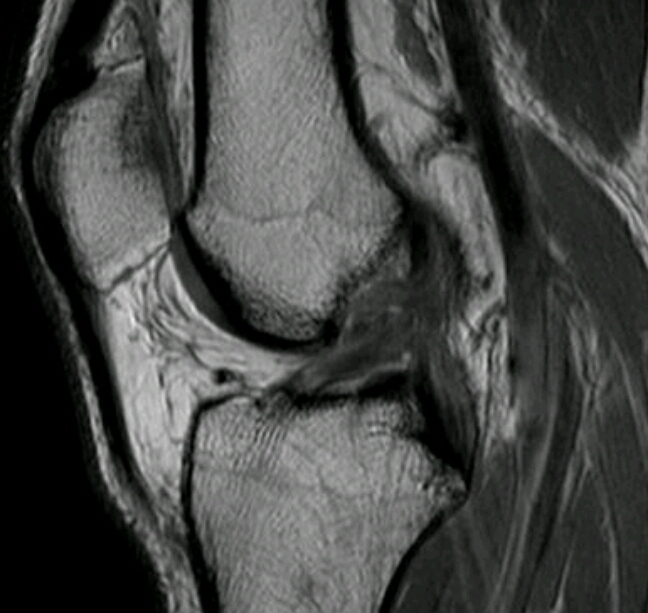

Name the disease. What are the signs of it?

Loss of superior joint space

Osteophyte formation

Subchondral cysts/geodes

Sclerosis

Buttressing

Joint deformity